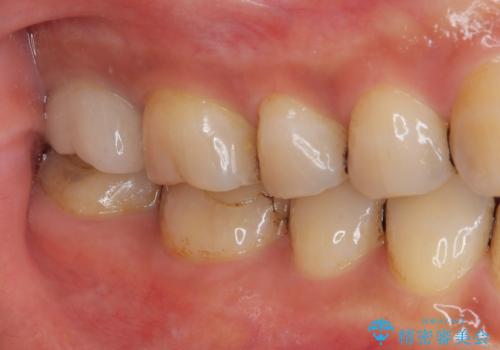

患者さまにはオールセラミッククラウンの色味、機能面共に満足していただけました。

今後はナイトガードを使用してもらいながら、メインテナンスで通っていただく予定です